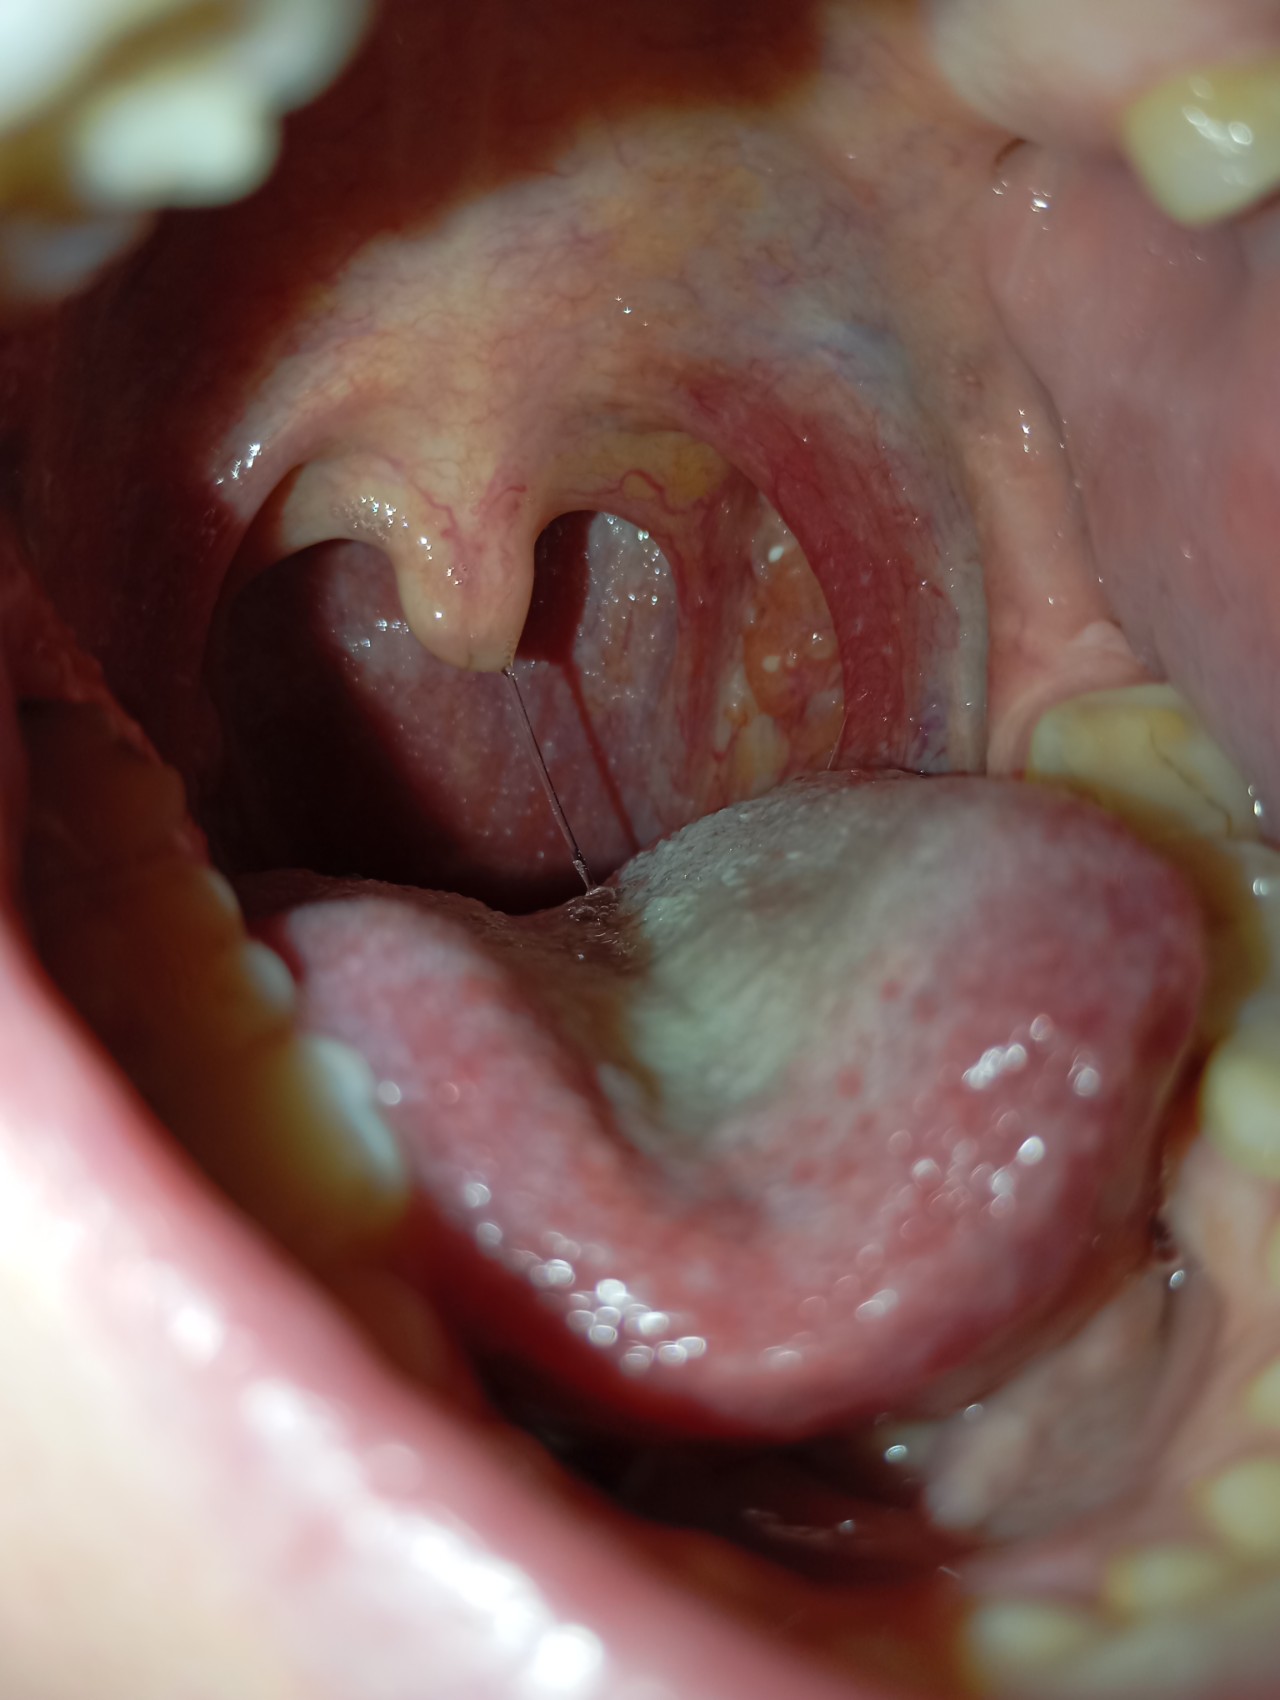

Здравствуйте, недавно стало першить в горле совсем немного, чуть покашливала. Посмотрела в зеркало и обнаружила около миндалины, чуть сбоку, какое -то образование, как маленький нарост, не отличающийся по цвету от остальной ткани. Подскпжира, пожалуйста, это нормально? Очень переживаю, спасибо!